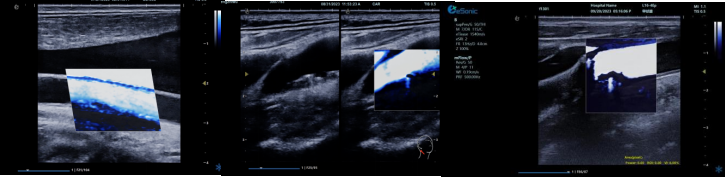

(三)mFlowTM 超微血流显像技术

mFlowTM 超微血流技术在小型机器上率先实现微米级细小血管识别与低速血流捕捉,以往仅高端台式机具备此功能。该技术专注于颈动脉粥样硬化斑块内血流评估,无需造影剂,具有高分辨率、低运动伪像和高帧频成像特点。其优势如下:

? 运用 3D 壁滤波技术智能分析信号,可探测常规超声难以捕捉的低速血流,灵敏度高。

? 依据 Staub 标准对检查结果分级,直观展示斑块内新生血管血流,为斑块稳定性评估提供新指标。

? 基于多普勒原理,进行频谱测量,并可进行VI指数测量,定量评估斑块内新生血管占比。

? 相较超声造影成像,无创便捷,为颈动脉易损斑块评估开辟新途径。

(四)iPlane Vascular 平面波超微细血流显像技术

iPlane Vascular 技术借助 OmniSound?平面波和 3D 壁滤波技术突破,提升超声多普勒分辨率并具备定量测量能力。优势如下:

? 显著提高对低速血流的敏感度,实现高分辨率、高帧频实时微血流成像(分辨率 30 微米、帧频 150 帧/s),动态显示斑块内新生血管血流。

? 基于多普勒原理进行频谱测量与 VI 指数计算,定量评估斑块内新生血管。

? 成像质量接近造影效果且无需造影剂,无创简便,增强诊断准确性,适用于细微血流变化场景。